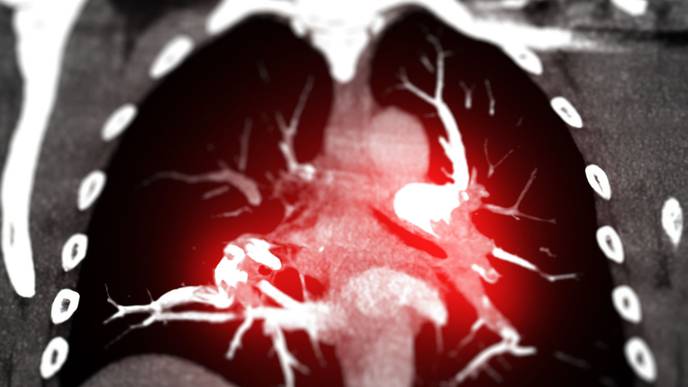

Almodóvar said those comorbidities include neurological and metabolic disorders, liver and kidney diseases, cancers and cardiovascular diseases. They also include pulmonary hypertension, which is currently the focus of her lab’s research. Pulmonary hypertension is a condition in the lungs caused by severe narrowing of the arteries. It increases the pressure in these arteries and affects the right side of the heart, which is not anatomically equipped to handle such high pressures. If the condition progresses without diagnosis or treatment, the result is often death due to right heart failure.

“The blood vessels in the lungs are severely affected in the presence of HIV, and this leads to serious illnesses in the lungs and heart,” Almodóvar explained. “In this study, we will conduct experiments to understand how HIV molecules change the way that lung molecules interact so that we can propose novel therapies to prevent lung diseases in people with HIV.”